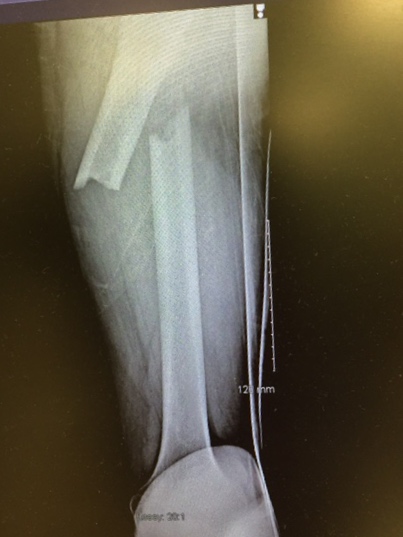

It’s been one year since I broke my femur – you can see the progress of my healing in this image:

I was in the ER in Santa Fe by 6:00PM – they did surgery ASAP: aligned the bones, drilled out the core, and installed an internal continuous rod, screwed everything together and stapled me up! I was in my room by 3AM.